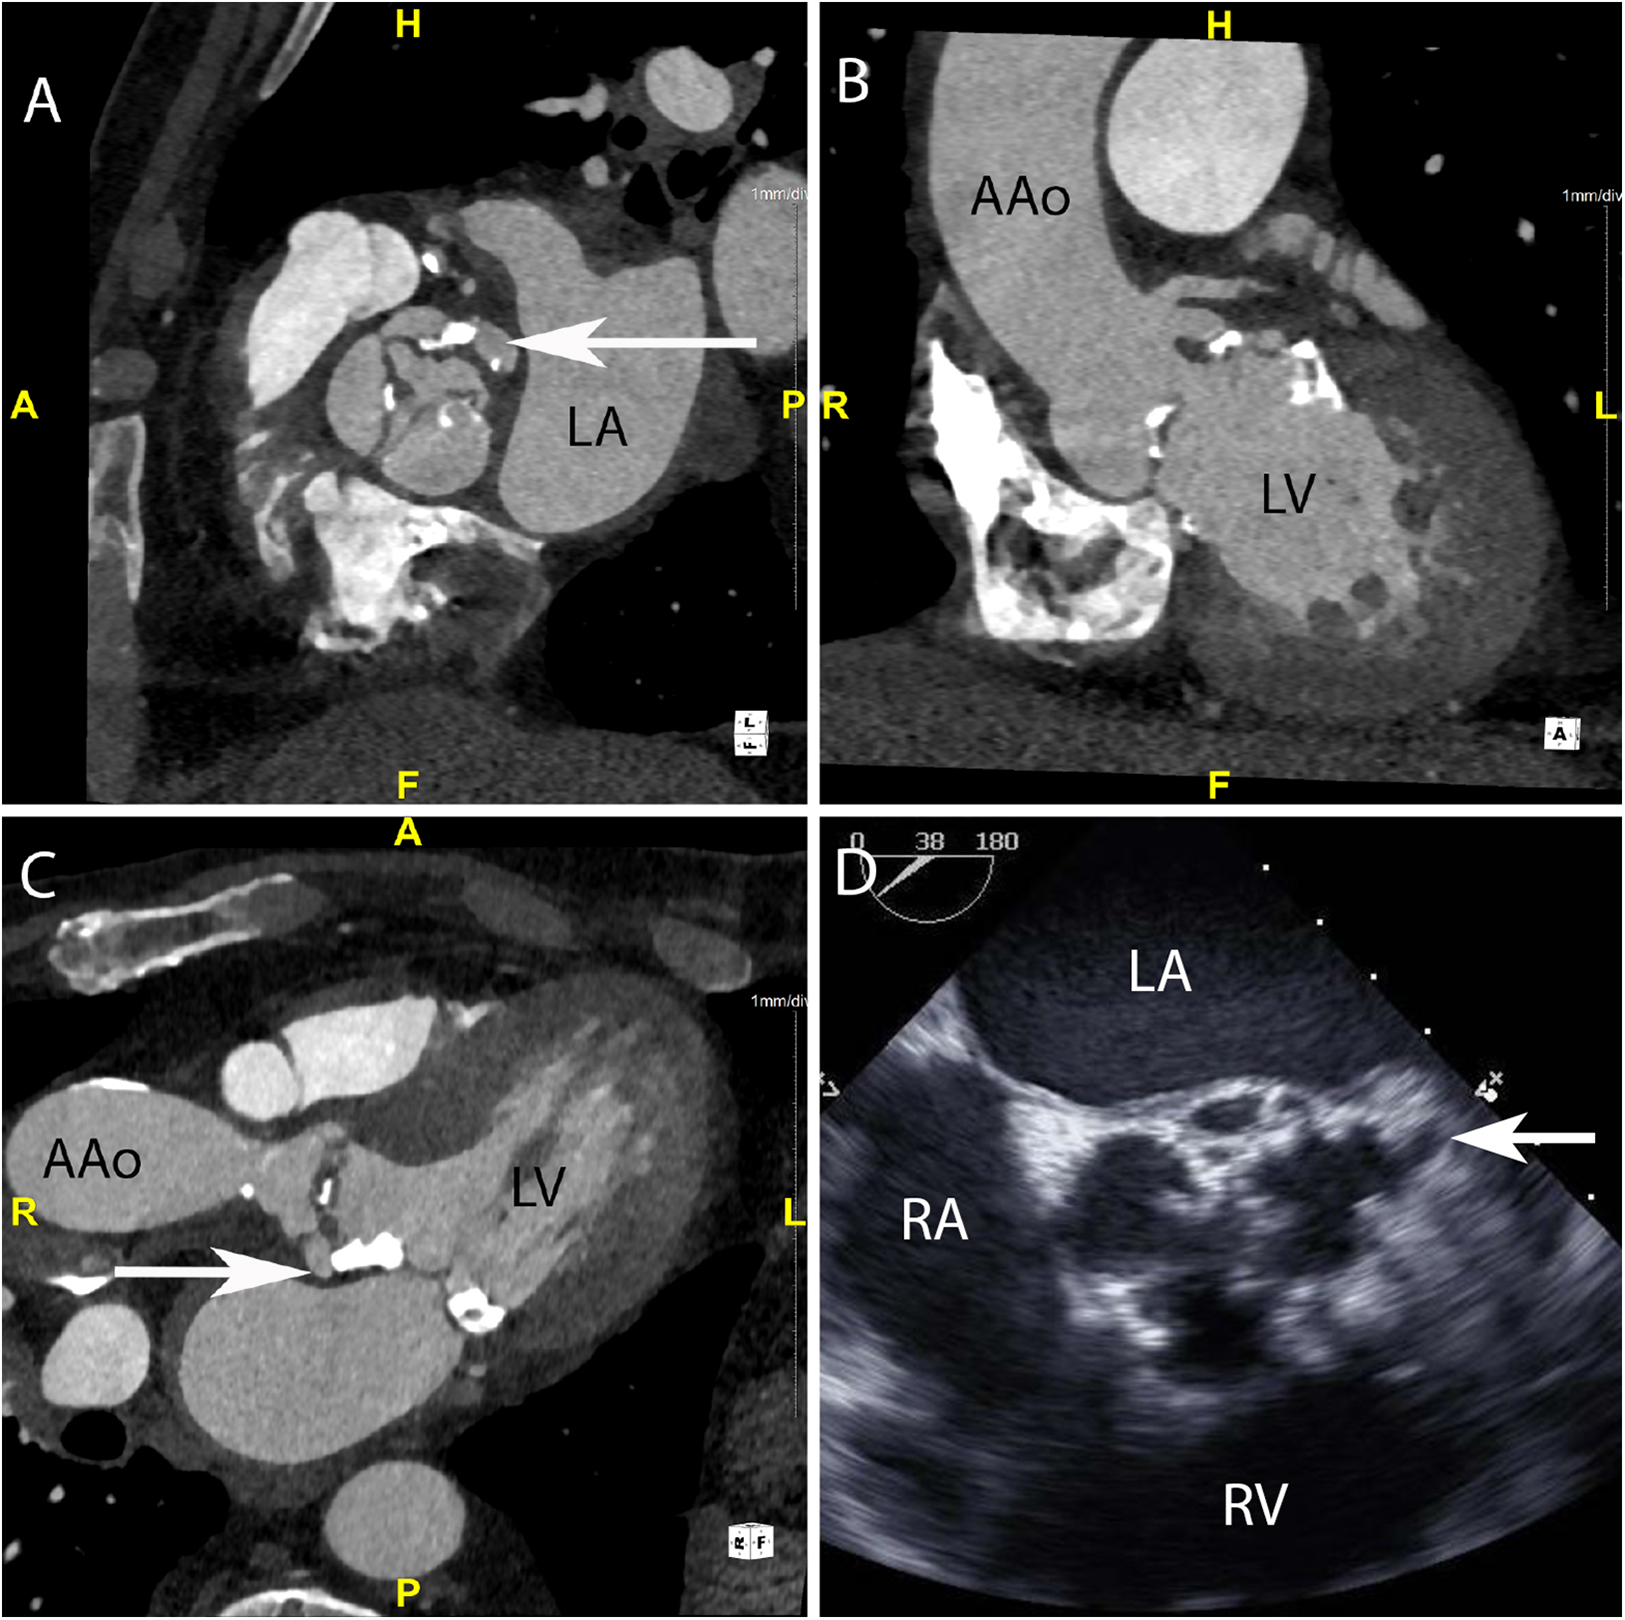

Figure 1

CASE 1 - A 75-year-old man presented feeling generally unwell with fever. Staphylococcus aureus was isolated from blood cultures (see text). LA, left atrium; LV, left ventricle; RA, right atrium; RV, right ventricle; AAo, ascending aorta.

A 75-year-old man presented feeling generally unwell with fever. Staphylococcus aureus was isolated from blood cultures. Cardiac CT was performed: An in-plane view (Figure 1A) of the aortic valve demonstrated a low-density soft tissue vegetation on all three cusps and a pseudoaneurysm (arrow) which communicated with the left coronary sinus (HU 420). Oblique coronal (Figure 1B) and axial (Figure 1C) views demonstrated that the vegetation was attached to both sides of the aortic valve cusps and showed the presence of a small pseudoaneurysm (arrow) that had been missed on TTE. Although aortic root abscesses and pseudoaneurysms are often used interchangeably in cardiac imaging, on CT a pseudoaneurysm is defined as a perivalvular cavity that is in communication with either a heart chamber or major blood vessel resulting from rupture of an abscess into that cavity. In contrast, an abscess is a closed cavity with necrosis and purulent material which appears as a perivalvular collection(s) of fluid encased in a thick layer of inflammatory tissue enhanced by the injection of contrast medium. Preceding TOE images (Figure 1D) taken in the mid-oesophageal aortic valve short axis view (ME AV SAX view) failed to accurately differentiate aortic valve calcification from small vegetations. There was a presumed small pseudoaneurysm communicating with the left coronary cusp (arrow) but its extent could not be determined.